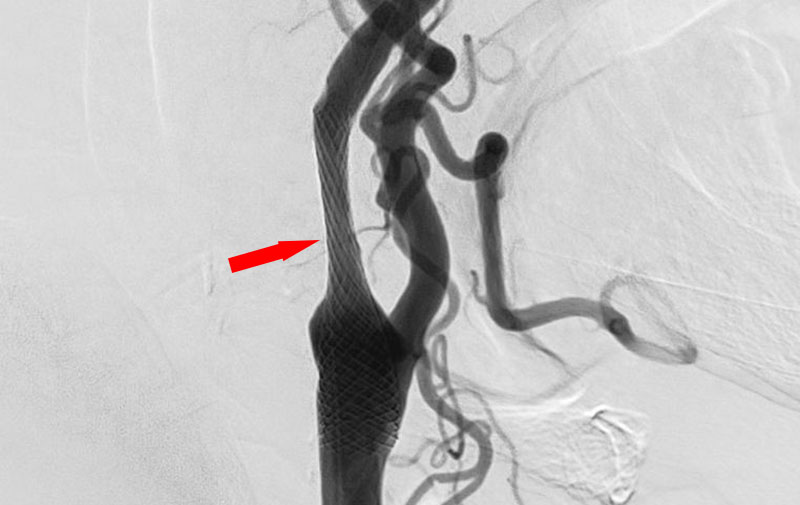

'21年9月

右内頚動脈狭窄症

70代

院内外来

No.1103 手術前

No.1103 手術中

No.1103 手術後